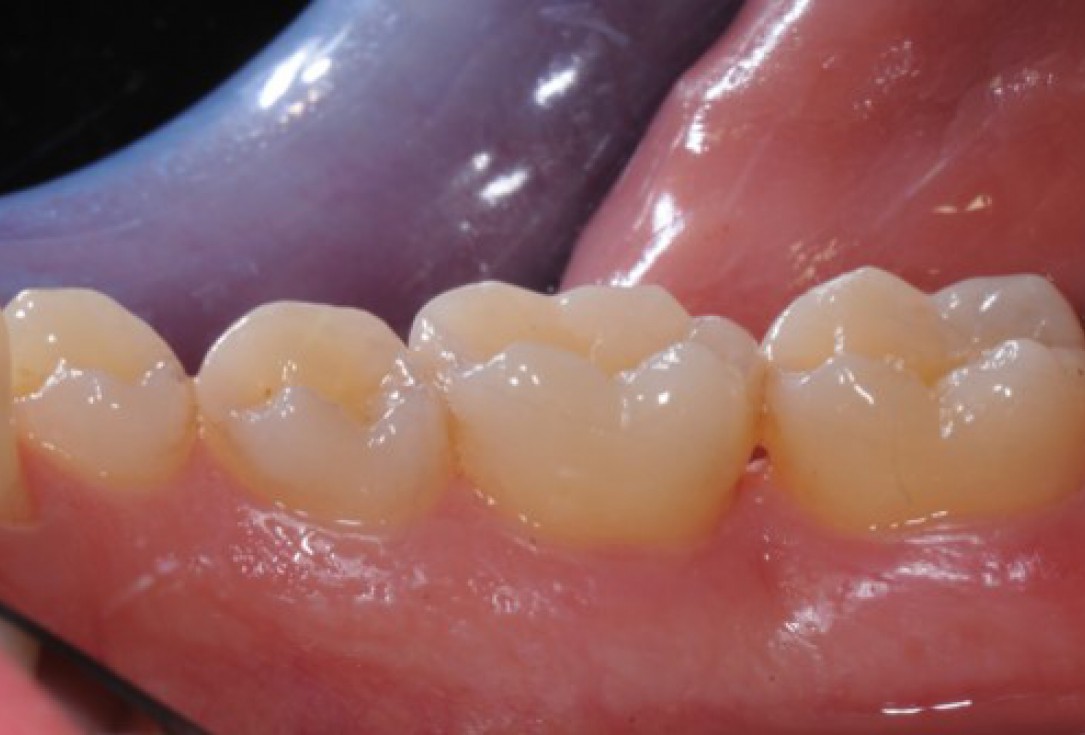

15/22 - Clinical situation 12 months post-operative. Buccal view.

Deep intrabony defects treated using Straumann® Emdogain® - Dr. M. Stefanini